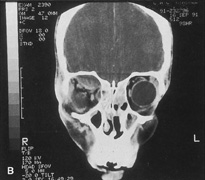

Magnetic resonance imaging is useful in selected cases, especially when evaluating the orbital cranial junction. Significant bony artifact and a lack of orbital fat in the orbital apex make CT scan resolution of the orbital apex structures poor. Because cortical bone has low signal on MRI, there is no bone artifact when viewing the orbital apex on MRI. The lack of intervening fat in the apex to provide contrast is overcome on MRI because contrast is provided by the individual nuclear characteristics of each tissue so that the orbital apex structures are visualized well. Consequently, conditions that affect the optic nerve and chiasm, such as optic nerve meningioma and glioma, generally are evaluated with MRI rather than CT scan (Fig. 2).

Fig. 2. A. Axial orbital CT scan of right optic nerve meningioma. Note lack of detail in orbital apex. B. Axial orbital MR image, same patient. Note increased detail in orbital apex owing to lack of bone artifact. C. MRI with gadolinium contrast. Note extension into brain not easily appreciated with CT scanning or MRI without contrast.